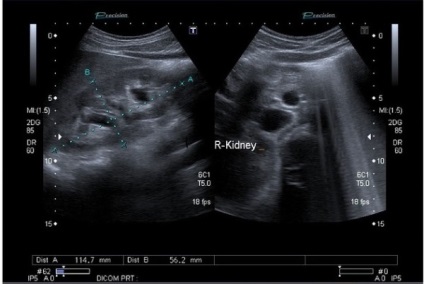

- Méretek. A normális emberi veséhez a következő paraméterekkel:

L (hossz) = 100-120 mm-es;

B (szélesség) = 50-60 mm;

S (vastagság) = 50-50 mm;

S parenchymás réteg = 20-25 mm;

S = 1,5 mm a kapszulában.

Vese Súly 1 között változik 120 g-200 g